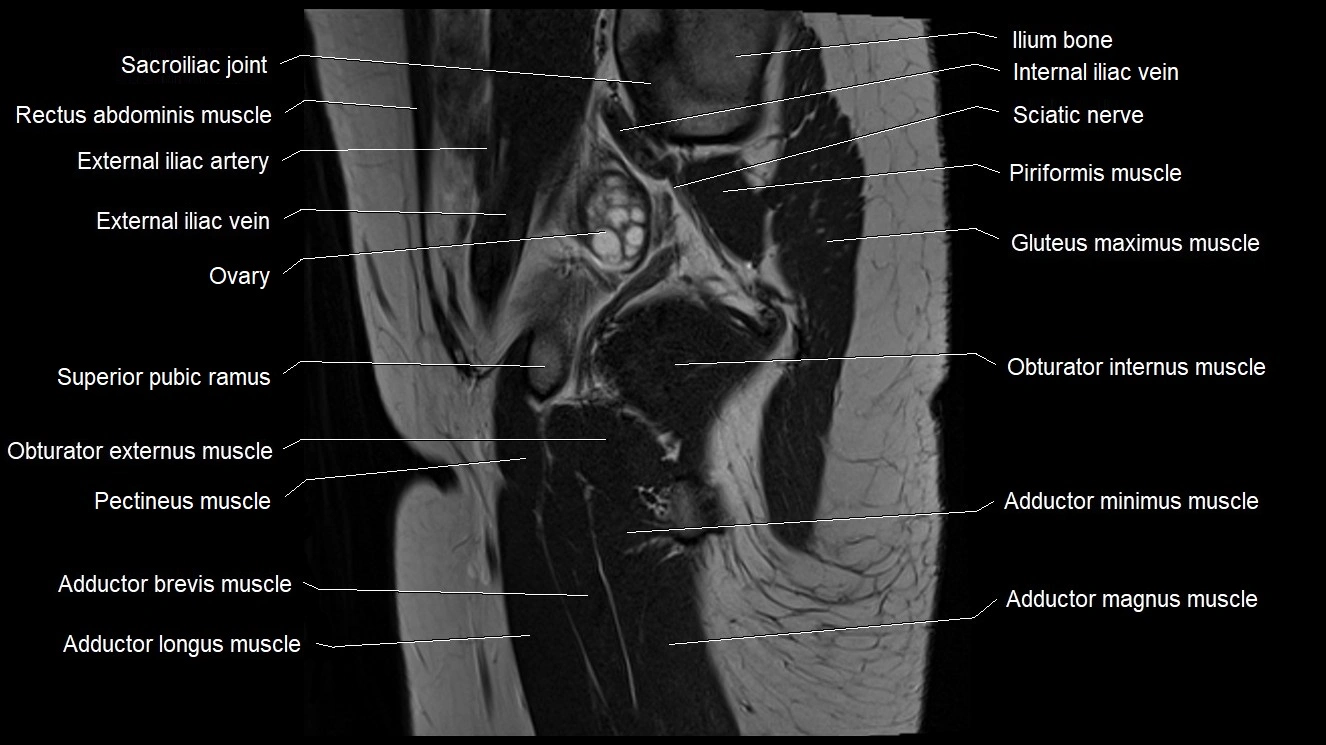

- Adductor brevis muscle

- Adductor longus muscle

- Adductor magnus muscle

- Adductor minimus muscle

- External iliac artery

- External iliac vein

- Gluteus maximus muscle

- Obturator externus muscle

- Obturator internus muscle

- Ovaries

- Pectineus muscle

- Sacroiliac joint

- Superior pubic ramus